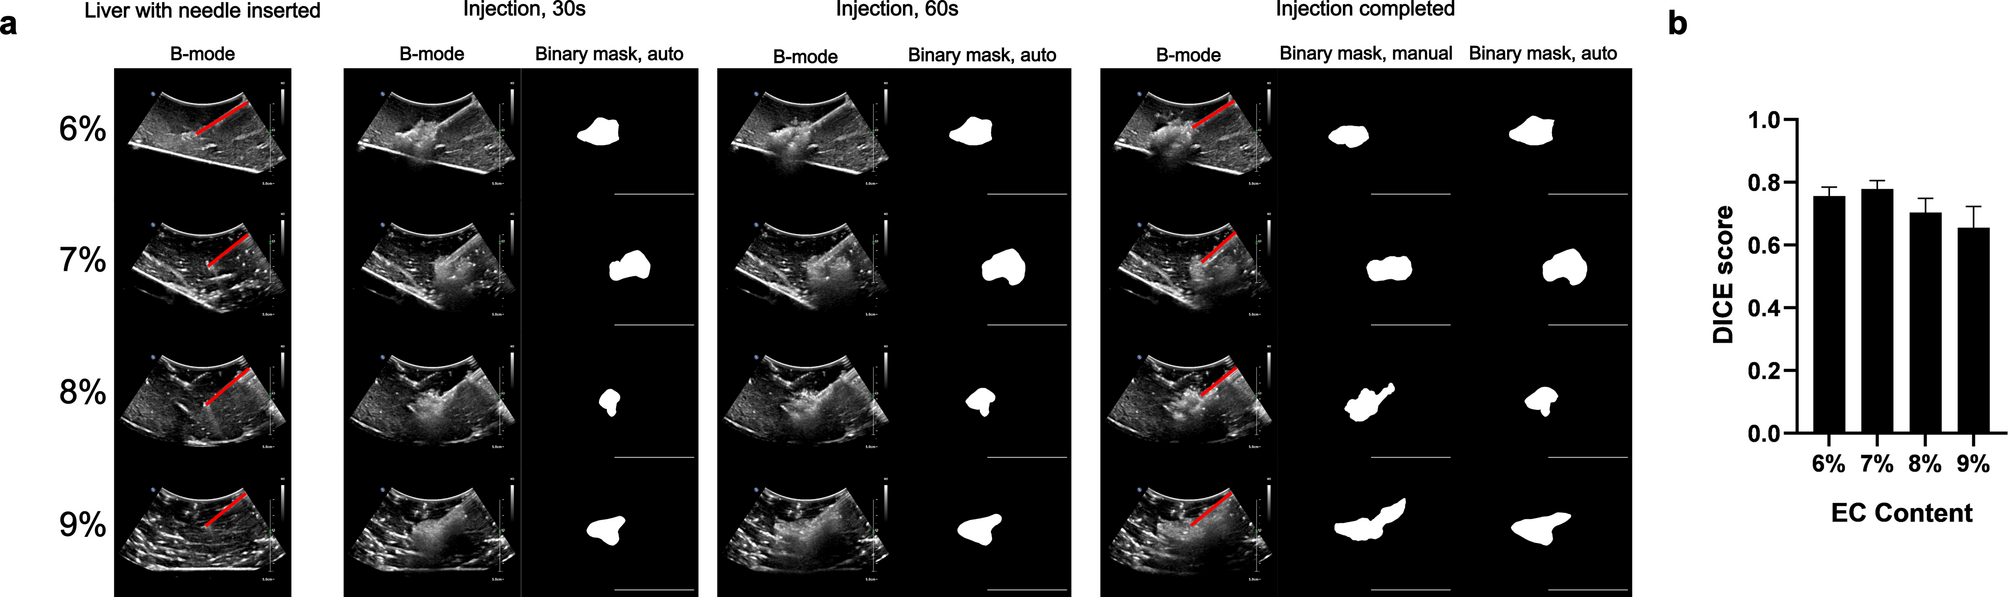

Fig. 5

Visibility of different concentrations of EC-ethanol in excised bovine liver. (a) Representative B-mode images and corresponding binary masks of EC-ethanol throughout its injection procedure illustrate the real-time depot formation and immediate echogenicity of the gel distribution. Red lines denote needle path before and after injection. Scale barsā=ā5Ā cm. (b) Dice scores for measuring the similarity between binary masks generated from manual depot segmentation vs. automatic segmentation. Nā=ā4.